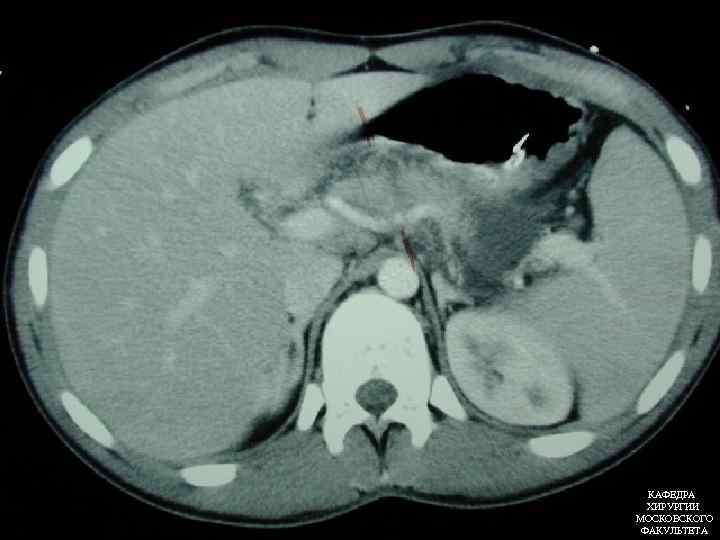

КОМПЬЮТЕРНАЯ ТОМОГРАФИЯ Позволяет оценить объём поражения поджелудочной железы Выявляет степень некроза поджелудочной железы Позволяет прогнозировать течение болезни КАФЕДРА ХИРУРГИИ МОСКОВСКОГО ФАКУЛЬТЕТА

КОМПЬЮТЕРНАЯ ТОМОГРАФИЯ Позволяет оценить объём поражения поджелудочной железы Выявляет степень некроза поджелудочной железы Позволяет прогнозировать течение болезни КАФЕДРА ХИРУРГИИ МОСКОВСКОГО ФАКУЛЬТЕТА

КАФЕДРА ХИРУРГИИ МОСКОВСКОГО ФАКУЛЬТЕТА

КАФЕДРА ХИРУРГИИ МОСКОВСКОГО ФАКУЛЬТЕТА

КОМПЬЮТЕРНАЯ ТОМОГРАФИЯ • А. Нормальные размеры и контрастирование железы • B. Увеличение в размерах • C. Перипанкреатит с воспалительными изменениями жировой ткани • D. С + наличие жидкости в переднем параренальном пространстве • E. D + наличие жидкости в сальниковой сумке Balthazar КАФЕДРА ХИРУРГИИ МОСКОВСКОГО ФАКУЛЬТЕТА

КОМПЬЮТЕРНАЯ ТОМОГРАФИЯ • А. Нормальные размеры и контрастирование железы • B. Увеличение в размерах • C. Перипанкреатит с воспалительными изменениями жировой ткани • D. С + наличие жидкости в переднем параренальном пространстве • E. D + наличие жидкости в сальниковой сумке Balthazar КАФЕДРА ХИРУРГИИ МОСКОВСКОГО ФАКУЛЬТЕТА

КОМПЬЮТЕРНАЯ ТОМОГРАФИЯ • А=0 • В=1 • С=2 • D=3 • Е=4 • Отсутствие некроза=0 • Некроз до 13 поджелудочной железы=2 • Некроз 50% поджелудочной железы=4 • Некроз >50% поджелудочной железы=6 КАФЕДРА ХИРУРГИИ МОСКОВСКОГО ФАКУЛЬТЕТА

КОМПЬЮТЕРНАЯ ТОМОГРАФИЯ • А=0 • В=1 • С=2 • D=3 • Е=4 • Отсутствие некроза=0 • Некроз до 13 поджелудочной железы=2 • Некроз 50% поджелудочной железы=4 • Некроз >50% поджелудочной железы=6 КАФЕДРА ХИРУРГИИ МОСКОВСКОГО ФАКУЛЬТЕТА

КОМПЬЮТЕРНАЯ ТОМОГРАФИЯ • 1 -2 балла – вероятность тяжелого панкреатита тяжелыми осложнениями невозможна • 3 -6 баллов – вероятность тяжелого панкреатита с тяжелыми осложнениями мала • 7 -10 баллов – вероятность тяжелого панкреатита с тяжелыми осложнениями 92%, летальность – 17% КАФЕДРА ХИРУРГИИ МОСКОВСКОГО ФАКУЛЬТЕТА

КОМПЬЮТЕРНАЯ ТОМОГРАФИЯ • 1 -2 балла – вероятность тяжелого панкреатита тяжелыми осложнениями невозможна • 3 -6 баллов – вероятность тяжелого панкреатита с тяжелыми осложнениями мала • 7 -10 баллов – вероятность тяжелого панкреатита с тяжелыми осложнениями 92%, летальность – 17% КАФЕДРА ХИРУРГИИ МОСКОВСКОГО ФАКУЛЬТЕТА